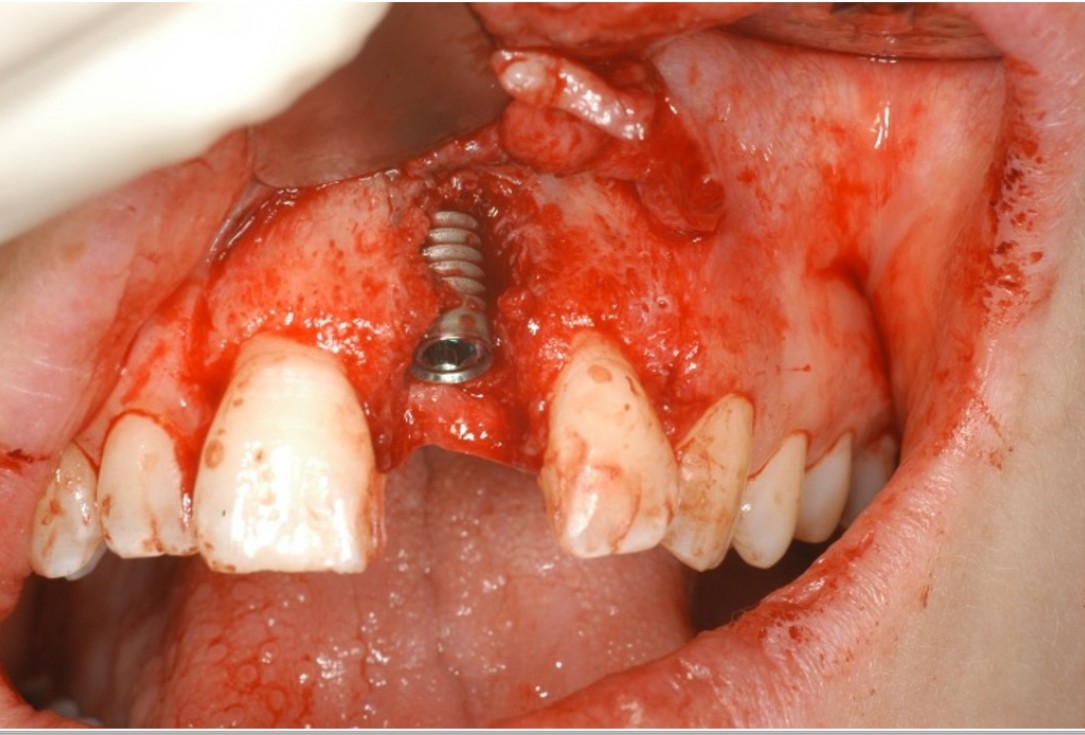

04/12 - Implant with extended dehiscence defectTreatment of dehiscence defect with cerabone® & Jason® membrane - Dr. M. Steigmann